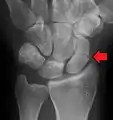

![]() | |

| An X-ray showing a fracture through the waist of the scaphoid | |